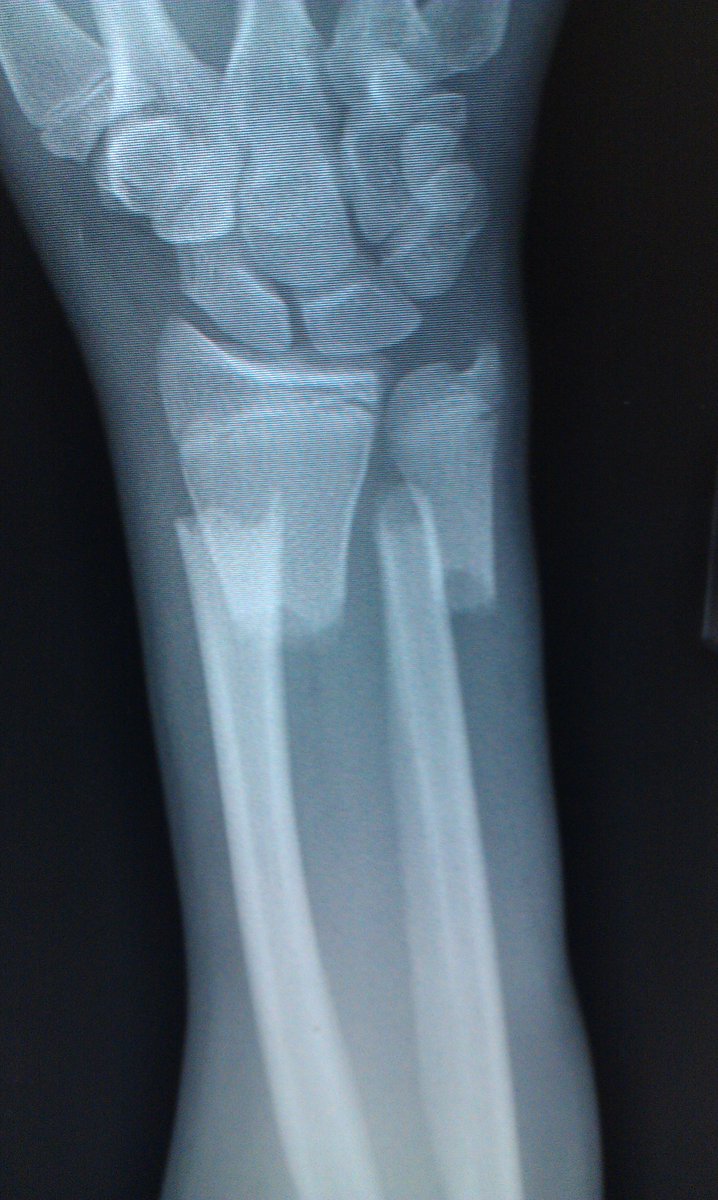

May 2012, beginning of high school summer break, I crashed on my dirt bike breaking the shit out of my right wrist & left collarbone

My wrist was so displaced it took 2 hours to set in the emergency room, that sucked

Here are some photos I could find